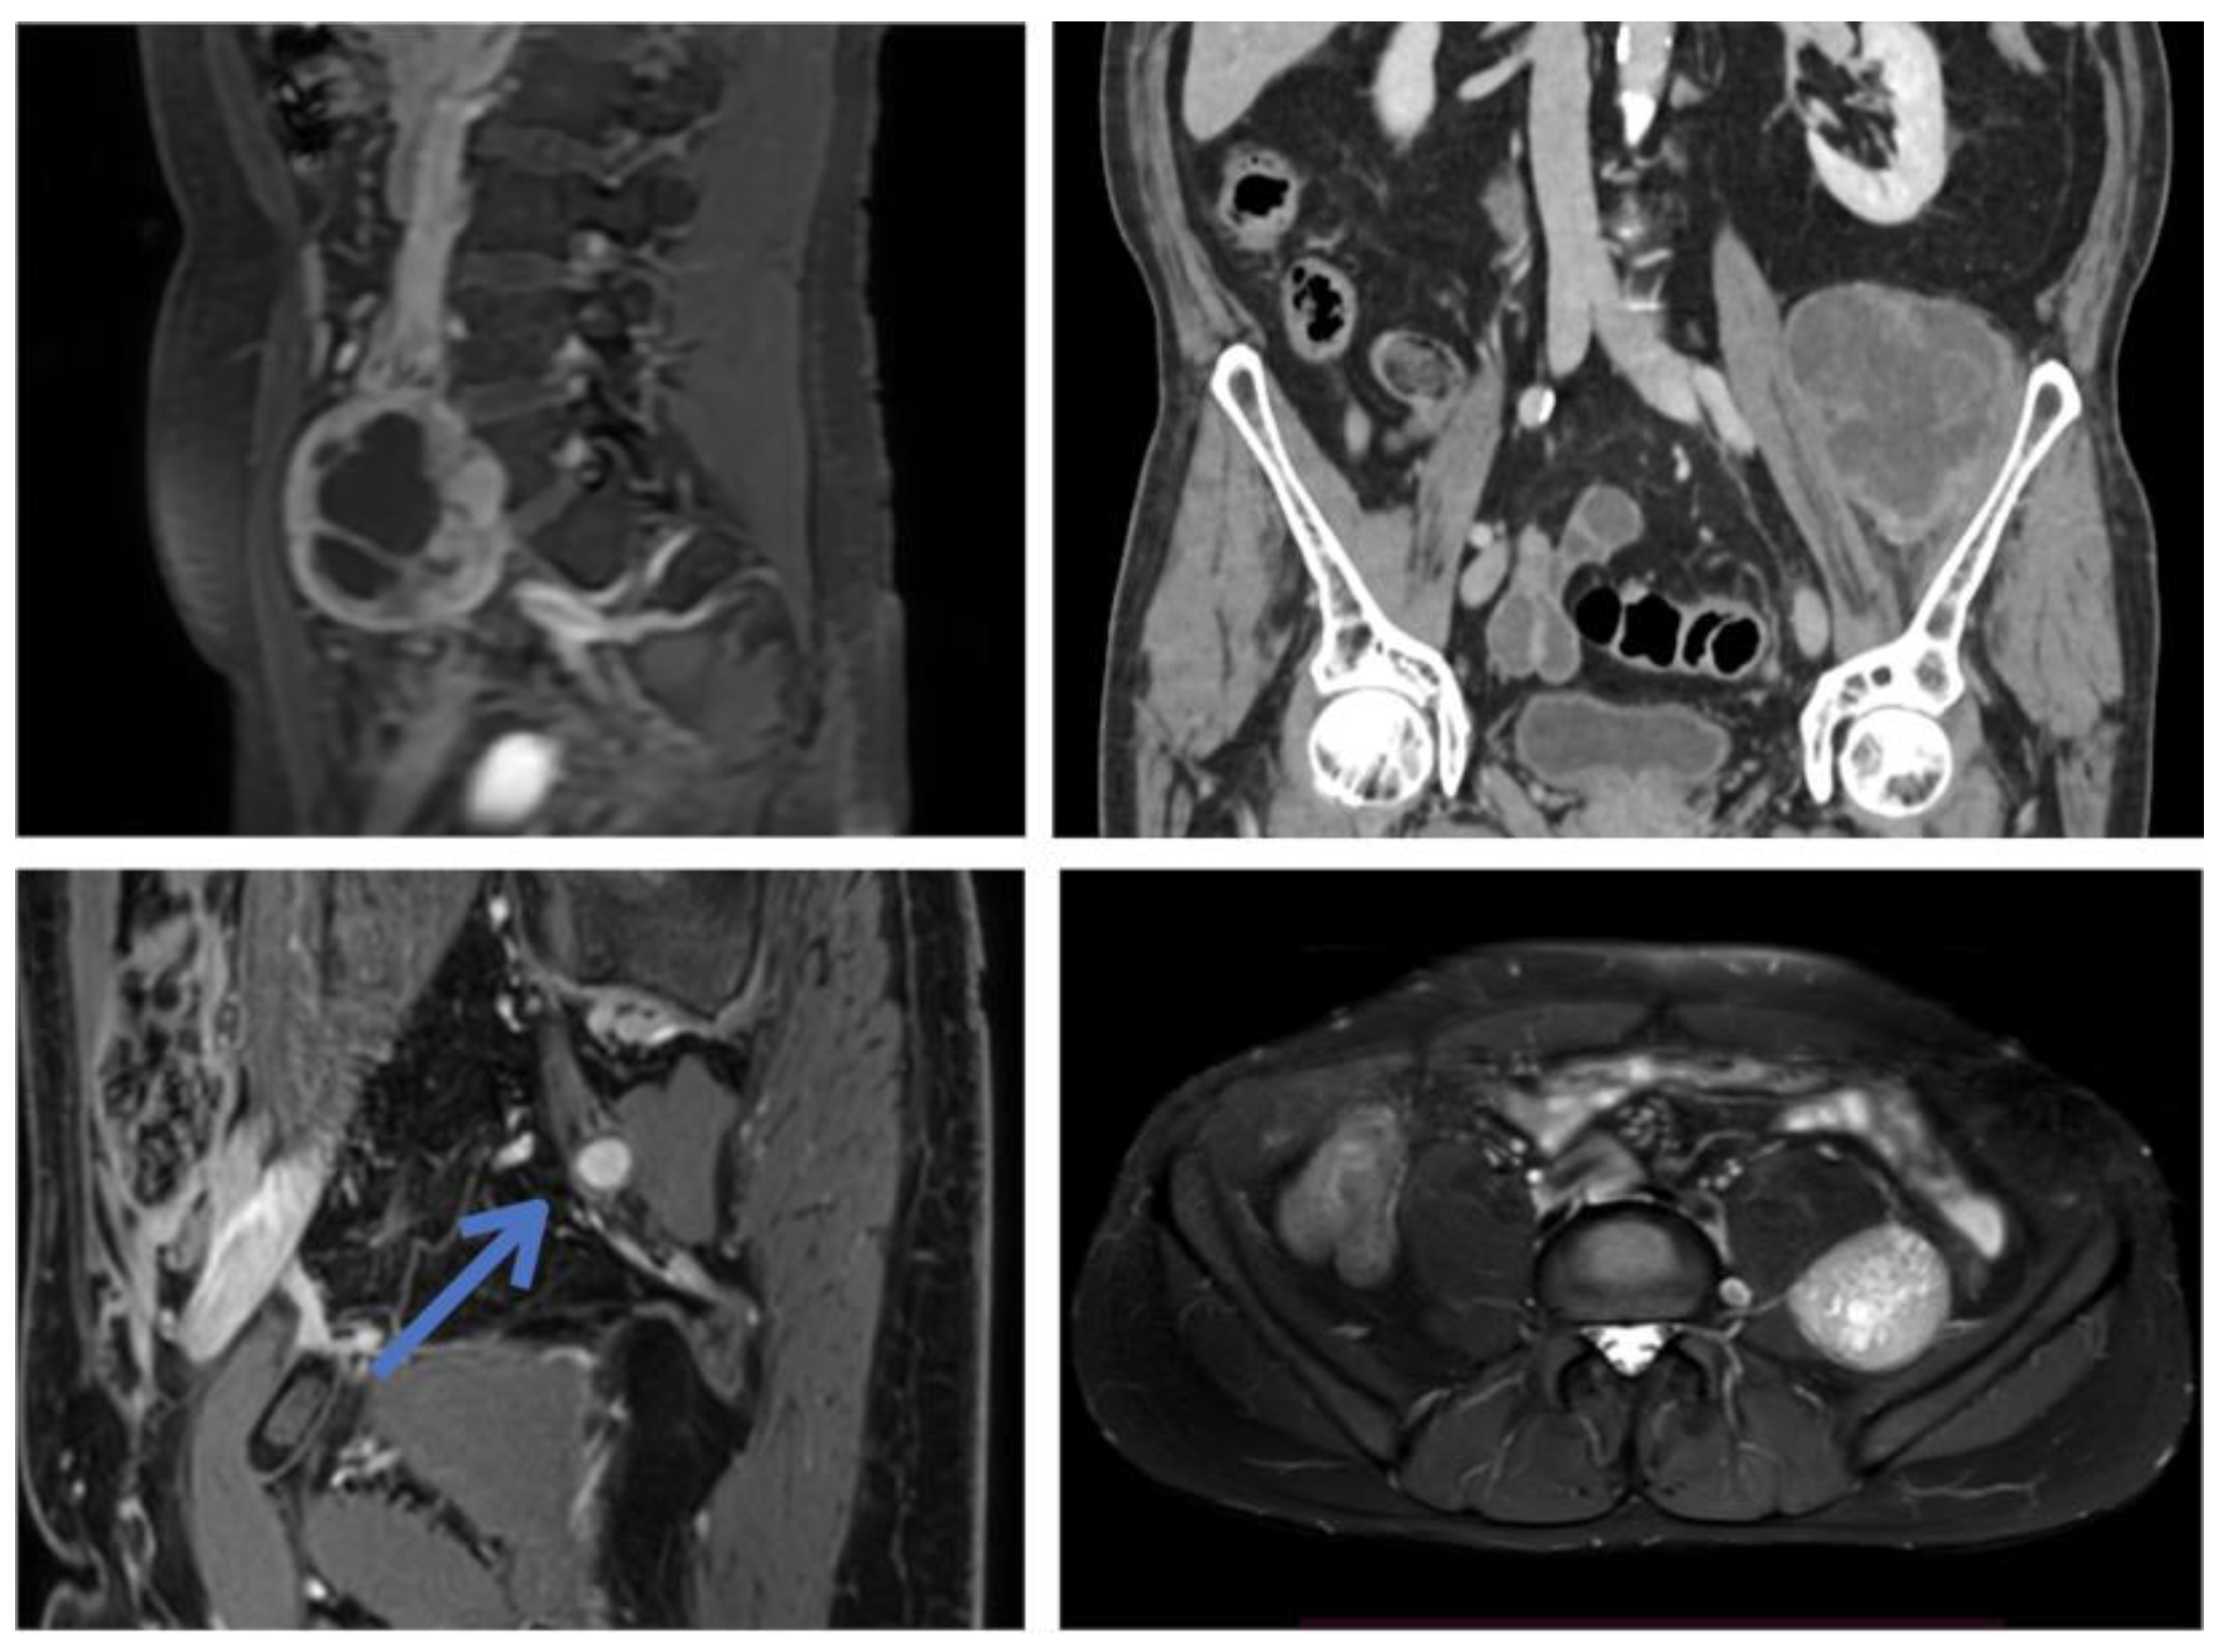

| Patient 1 | 55, M | Right obturator nerve, postero-lateral to psoas | S | 40 | None | Lateral retroperitoneal | 300 | 850 mL, no | 108 | Right medial thigh hypoesthesia | No, no | No |

| Patient 5 | 36, F | Sacral plexus (S1-S2), pelvic presacral | S | 130 | Left sciatic hypoestesia | Lower midline laparotomy; retroperitoneal | 480 | 3000 mL; yes | 30 | Ambulating on P.O. day 1; no new deficits; paresthesias on sciatic territory (improving) | Yes; no | Yes (open) |

| Patient 6 | 56, F | Left sciatic nerve, pelvis lateral to sacrum | S | 50 | Left sciatic pain | Pfannestiel incision; transperitoneal | 420 | 500 mL; no | 24 | Ambulating on P.O. day 1; no new deficits; pain remission; paresthesias on sciatic territory (improving) | Yes; no | Yes (open) |

| Patient 9 | 45, M | Sacral plexus; midline sacral promontory | S | 75 | Lower abdominal pain; abdominal mass | Lower midline laparotomy; transperitoneal | 150 | 200 mL; no | 18 | Ambulating on P.O. day 1; no new deficits | No; no | Yes (percutaneous) |